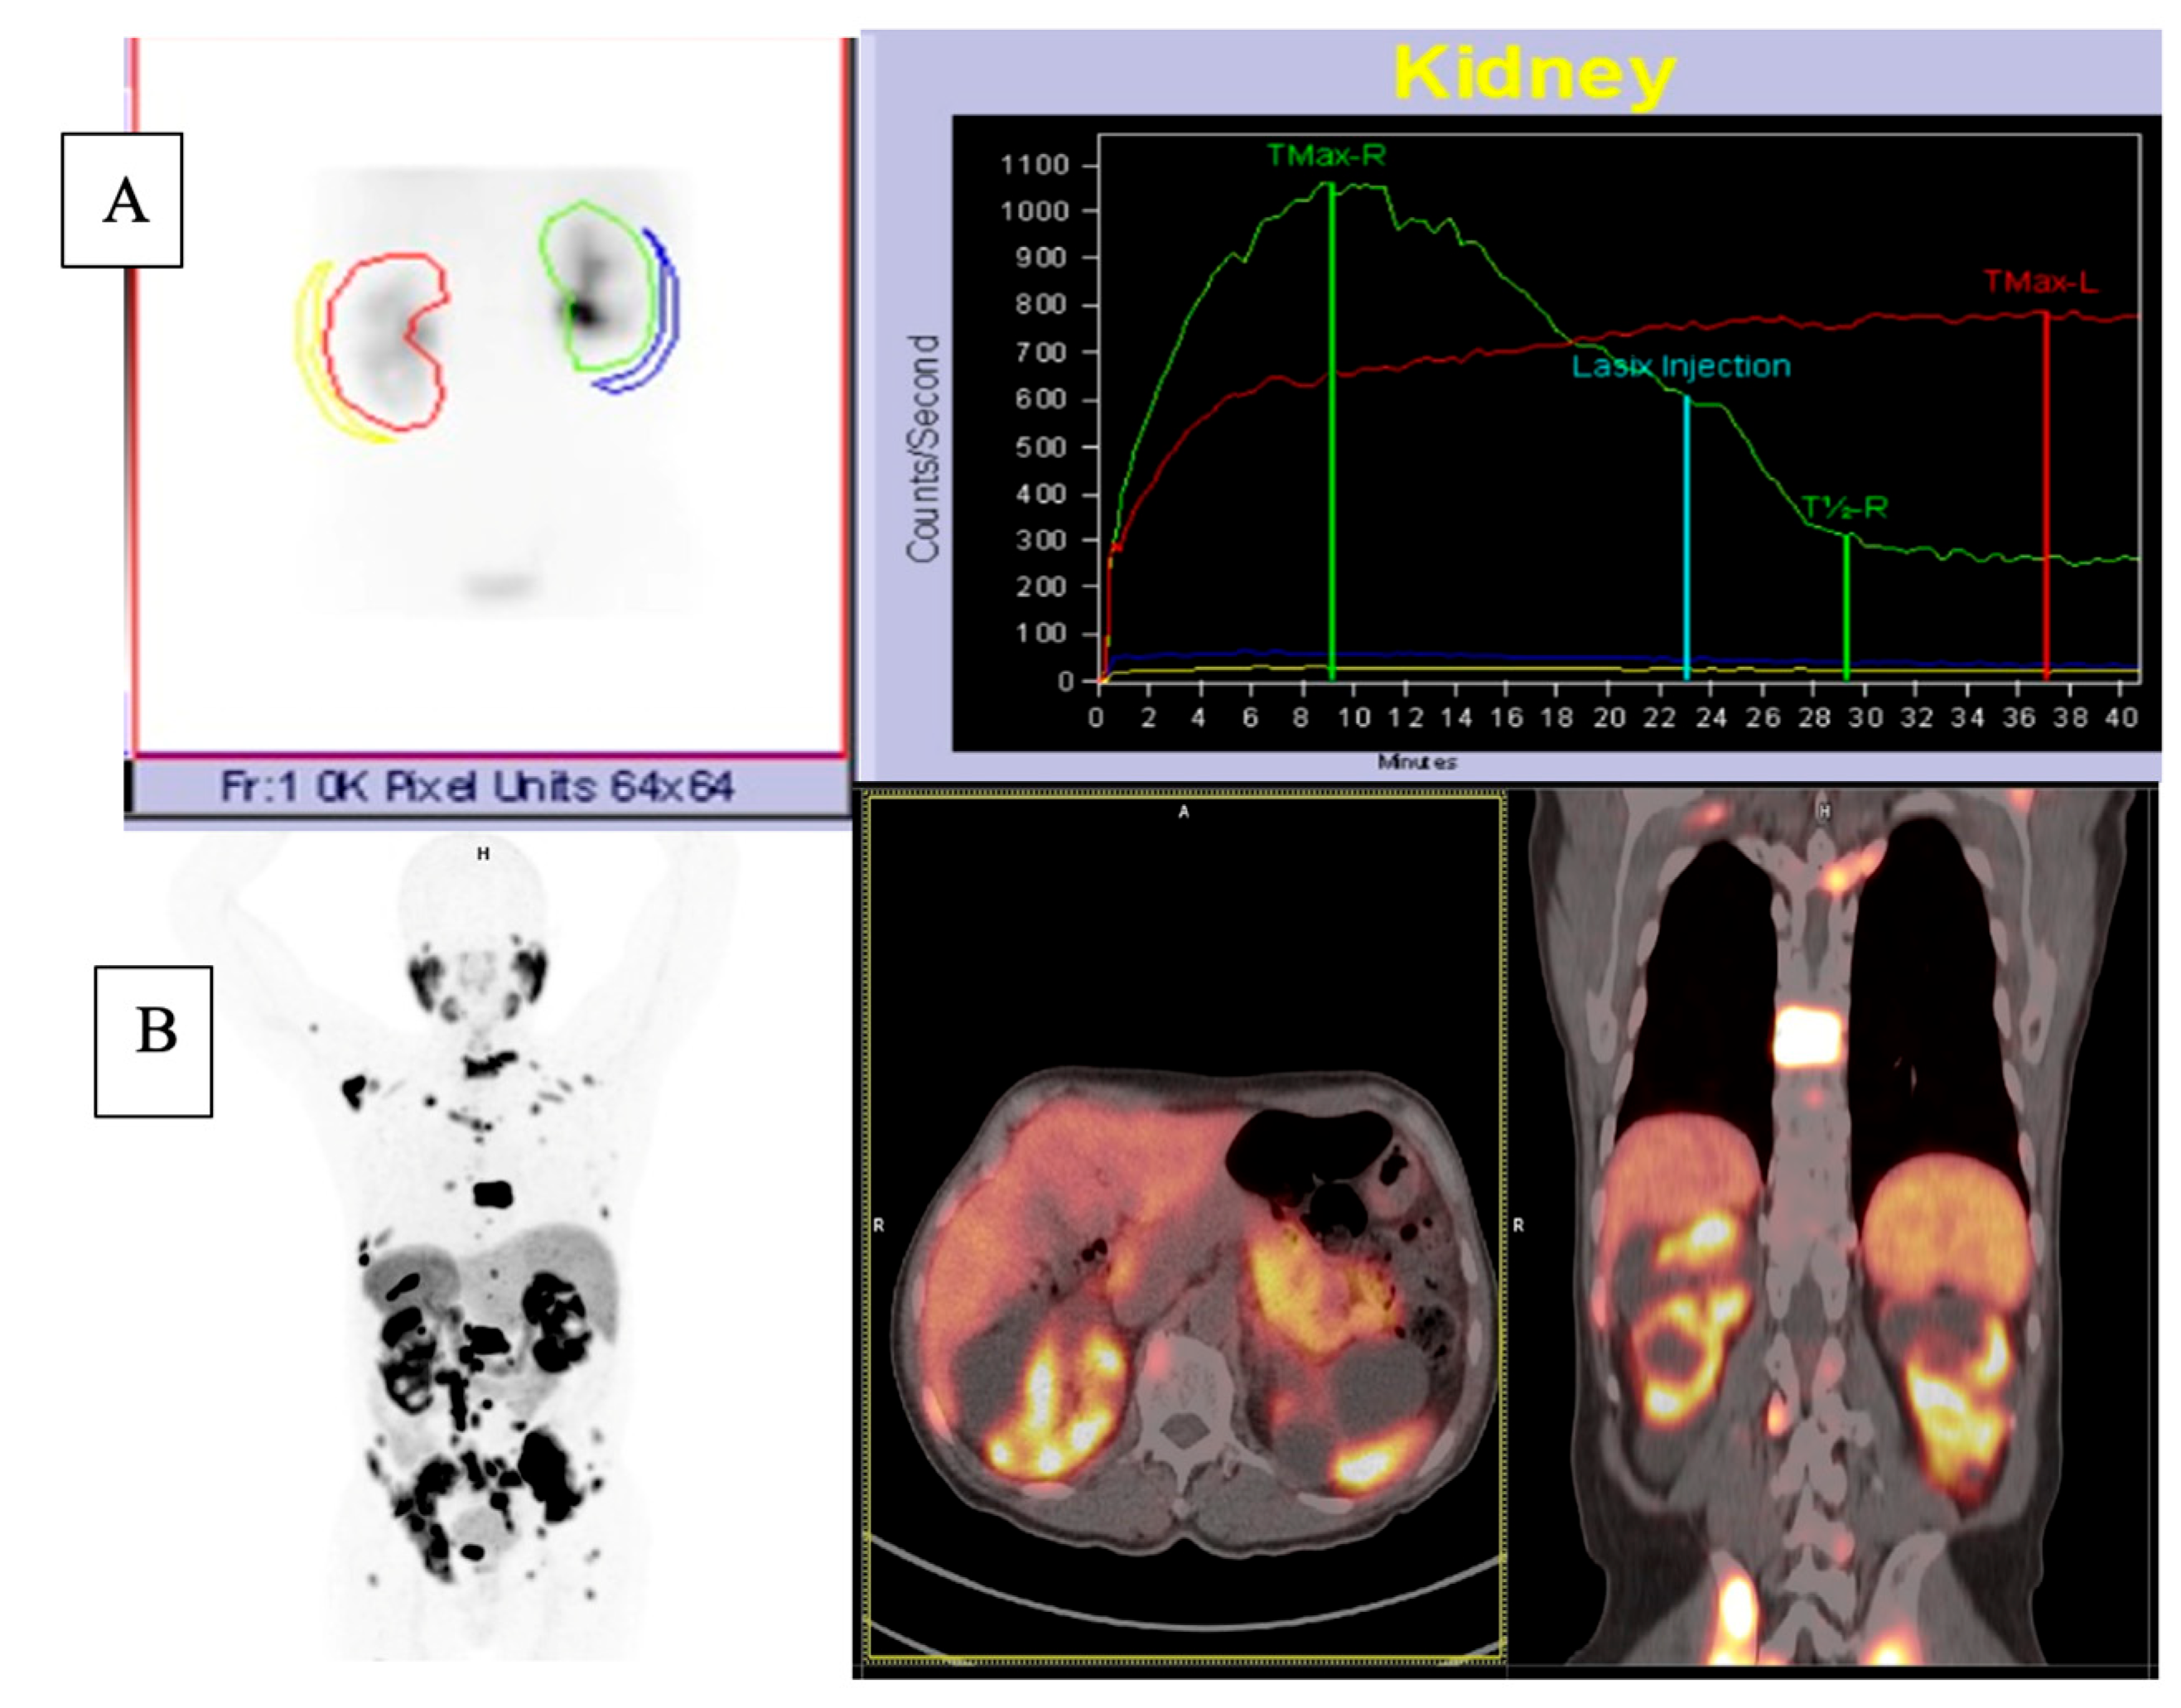

2.1.1. 68Ga-PSMA PET/CT

2.1.2. 68Ga-PSMA PET/CT Image Analysis

2.1.3. 99mTc-MAG3 Renal Scintigraphy

3.3. Comparison of Morphological Abnormalities